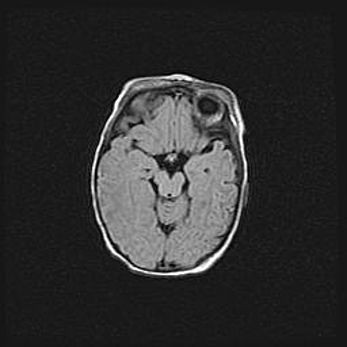

Наружная гидроцефалия с возможной атрофией височных областей.

Возраст: 28 дней

Вес: 3670 г

Пол: мужской

Окружность головы: 38 см

Срок гестации: 40 недель

Гидроцефалия головного мозга у новорожденных – это заболевание, которое характеризуется скоплением избыточного количества спинномозговой жидкости в желудочковой системе головного мозга в результате затруднения её перемещения от места выработки к месту поглощения в кровеносную систему или вследствие нарушения абсорбции. При открытой наружной форме гидроцефалии у новорожденных расширяются и переполняются субарахноидные пространства.

При нормотензивных  формах,  которые,  как  правило,  являются  следствием  перенесенных ишемических  повреждений  паренхимы  мозга,  возможно  сочетание микроцефалии  с нормотензивной гидроцефалией. В основе данных изменений лежит атрофия больших полушарий с преимущественной  локализацией  в  лобно-височных  областях.